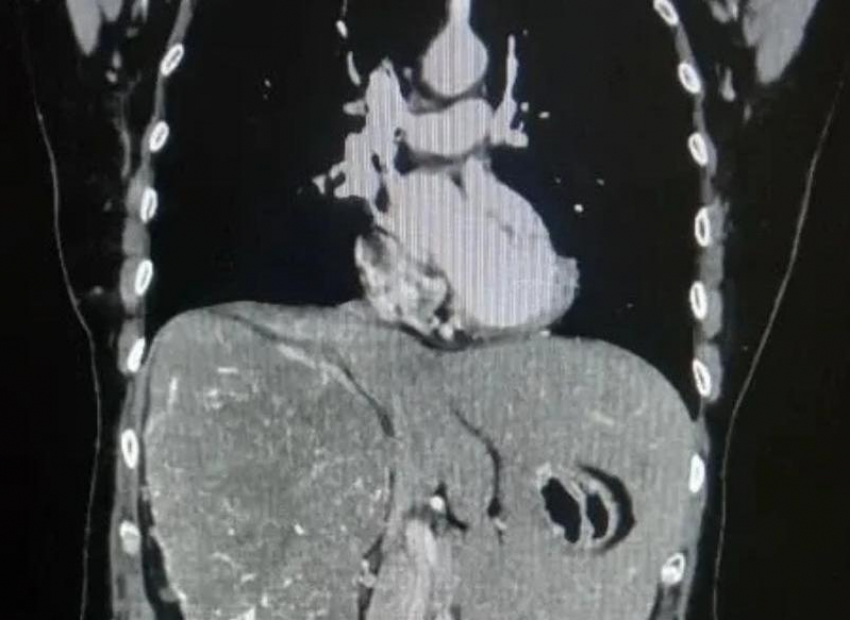

Врачи Волгоградского областного онкологического диспансера провели сложную операцию пациентке с гигантской опухолью почки. Новообразование достигло таких размеров, что сместило внутренние органы: печень оказалась вытеснена из правой части брюшной полости в левую.

Женщина долгое время жаловалась на тупую боль в пояснице и чувство тяжести в животе. После обследования с помощью компьютерной томографии врачи обнаружили крупную опухоль, которая практически полностью заняла правую сторону брюшной полости. Исследования показали, что функция правой почки была почти полностью утрачена. Размер новообразования составил более 20 сантиметров. Медики приняли решение о проведении операции. Из-за больших размеров опухоли выполнить вмешательство малоинвазивным способом было невозможно, поэтому хирурги провели открытую операцию — радикальное удаление правой почки.